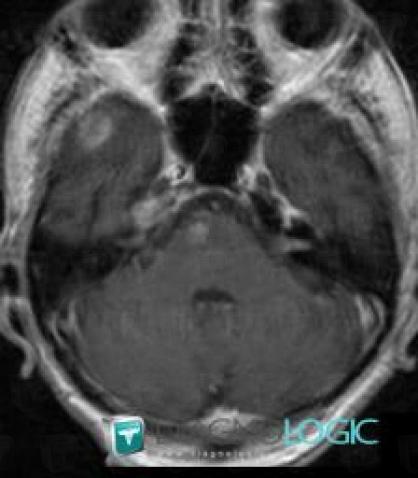

Métastase, Hémisphère cérébelleux, IRM

Voici les informations spécifiques à l'image clé ci dessus:

- Diagnostic Métastase, Localisation(s) Hémisphère cérébelleux, comportant les gammes Lésion cérébelleuse